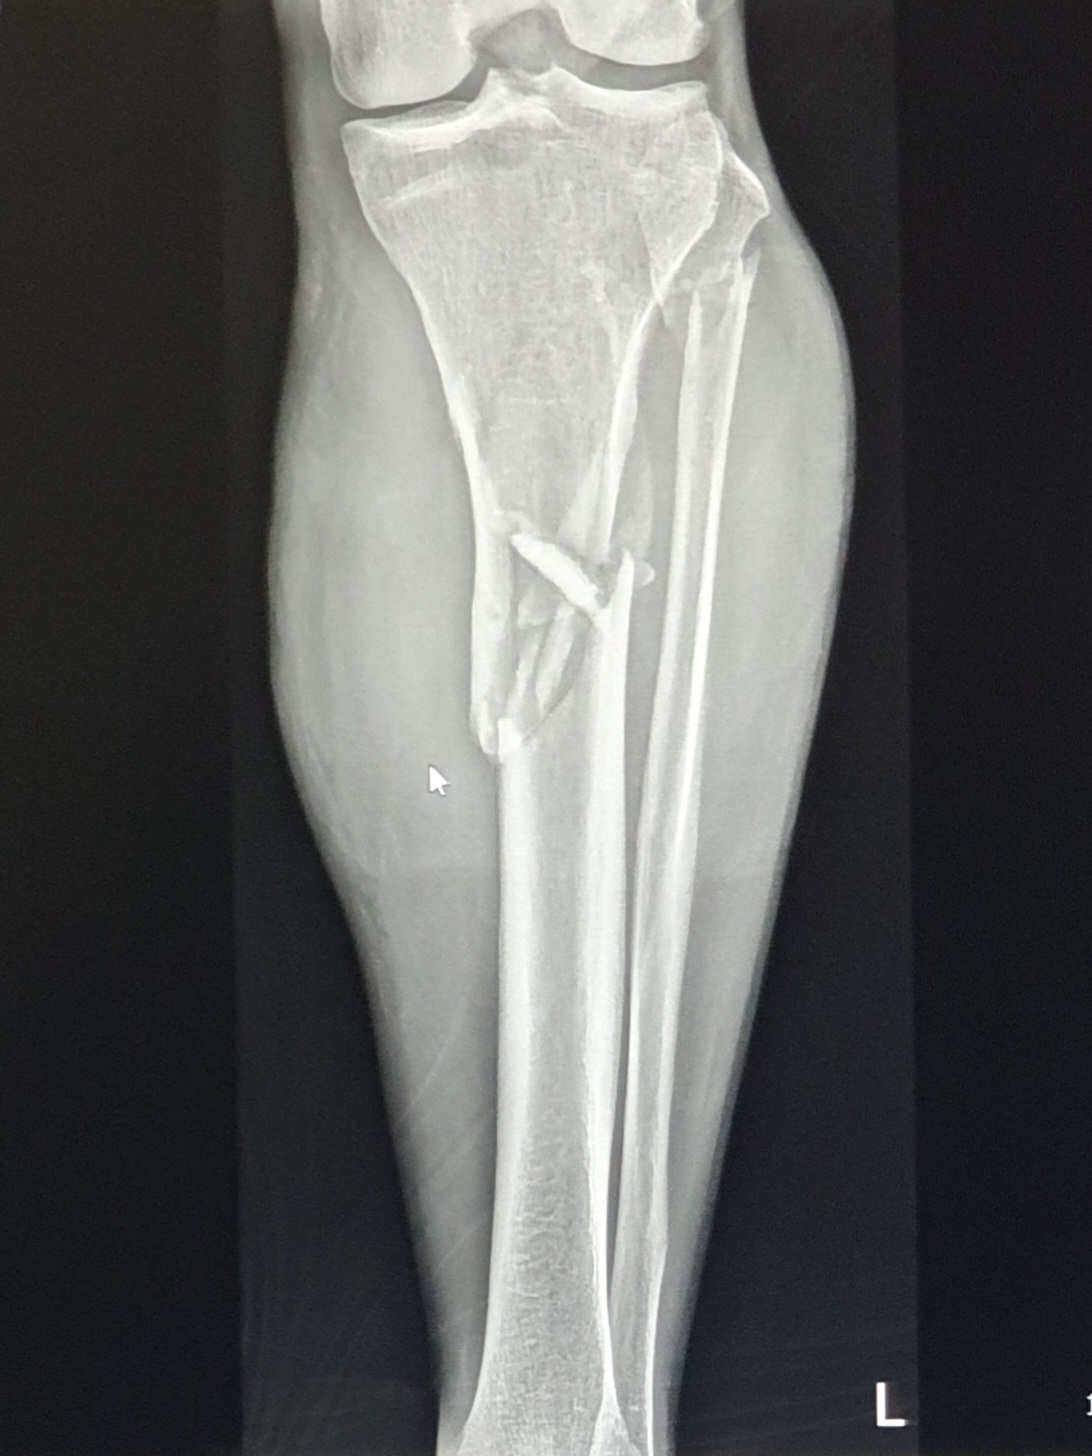

2022년 4일 1일 거짓말같이 낙상사고를 당한 후

4월5일 다리에 철심을 박는 대수술을 하였다.

화면에 올라온 X-ray 사진을 보니 8개월 전과는 확연히 달랐다.

낙상사고 당시의 비수술 상태에서 찍은 사진과 비교해서도 엄청난 진전이다.